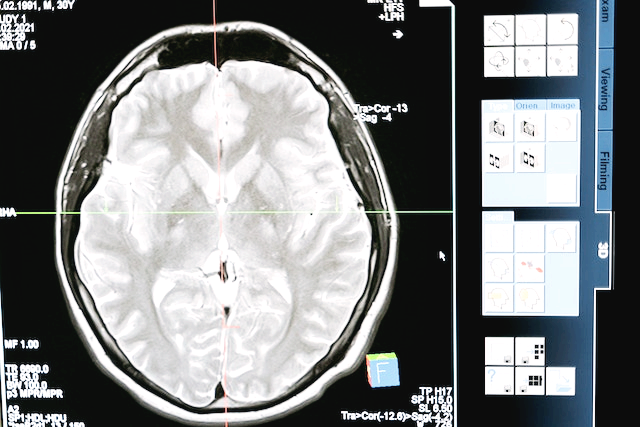

자폐 스펙트럼 장애를 진단하기 위해서는 부모의 발달력 청취와 임상 관찰이 중요합니다. 다양한 원인으로 인해 자폐가 표현될 수 있으므로 의학적 검사(염색체 검사, 대사 검사, 뇌파 검사, 뇌 MRI 등)가 필요할 수 있습니다. 또한 면담과 관찰 스케줄(ADOS) 및 진단 면담지(ADI-R) 등의 평가도 도움이 됩니다.